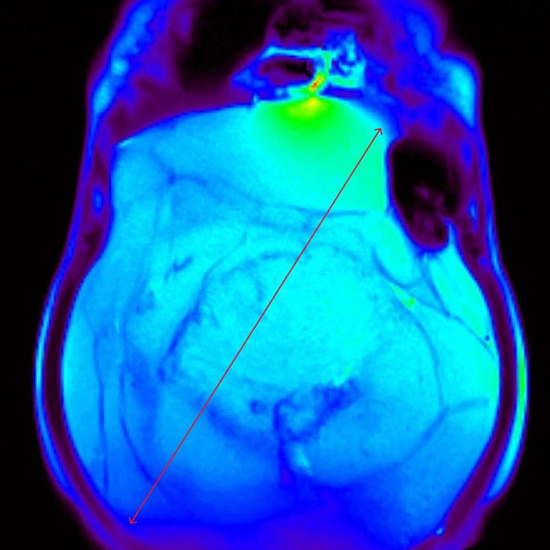

Пациентка 68 лет обратилась к хирургу с жалобами на увеличение размеров живота и снижение массы тела.

Накануне проведено УЗИ органов брюшной полости, выявлено образование брюшной полости.

С целью оценки образования, а также уточнения расположения и взаимоотношения с органами брюшной полости проведено МРТ органов брюшной полости с внутривенным контрастированием.

При МРТ было выявлено жиросодержащее внеорганное объемное образование больших размеров с множественными неравномерными накапливающими контрастный препарат перегородками, занимающее большую часть брюшной полости с признаками смещения прилежащих внутренних органов.

Учитывая особенности структуры образования, распространенность и расположение, находка расценена как липосаркома (злокачественная опухоль жировой ткани).